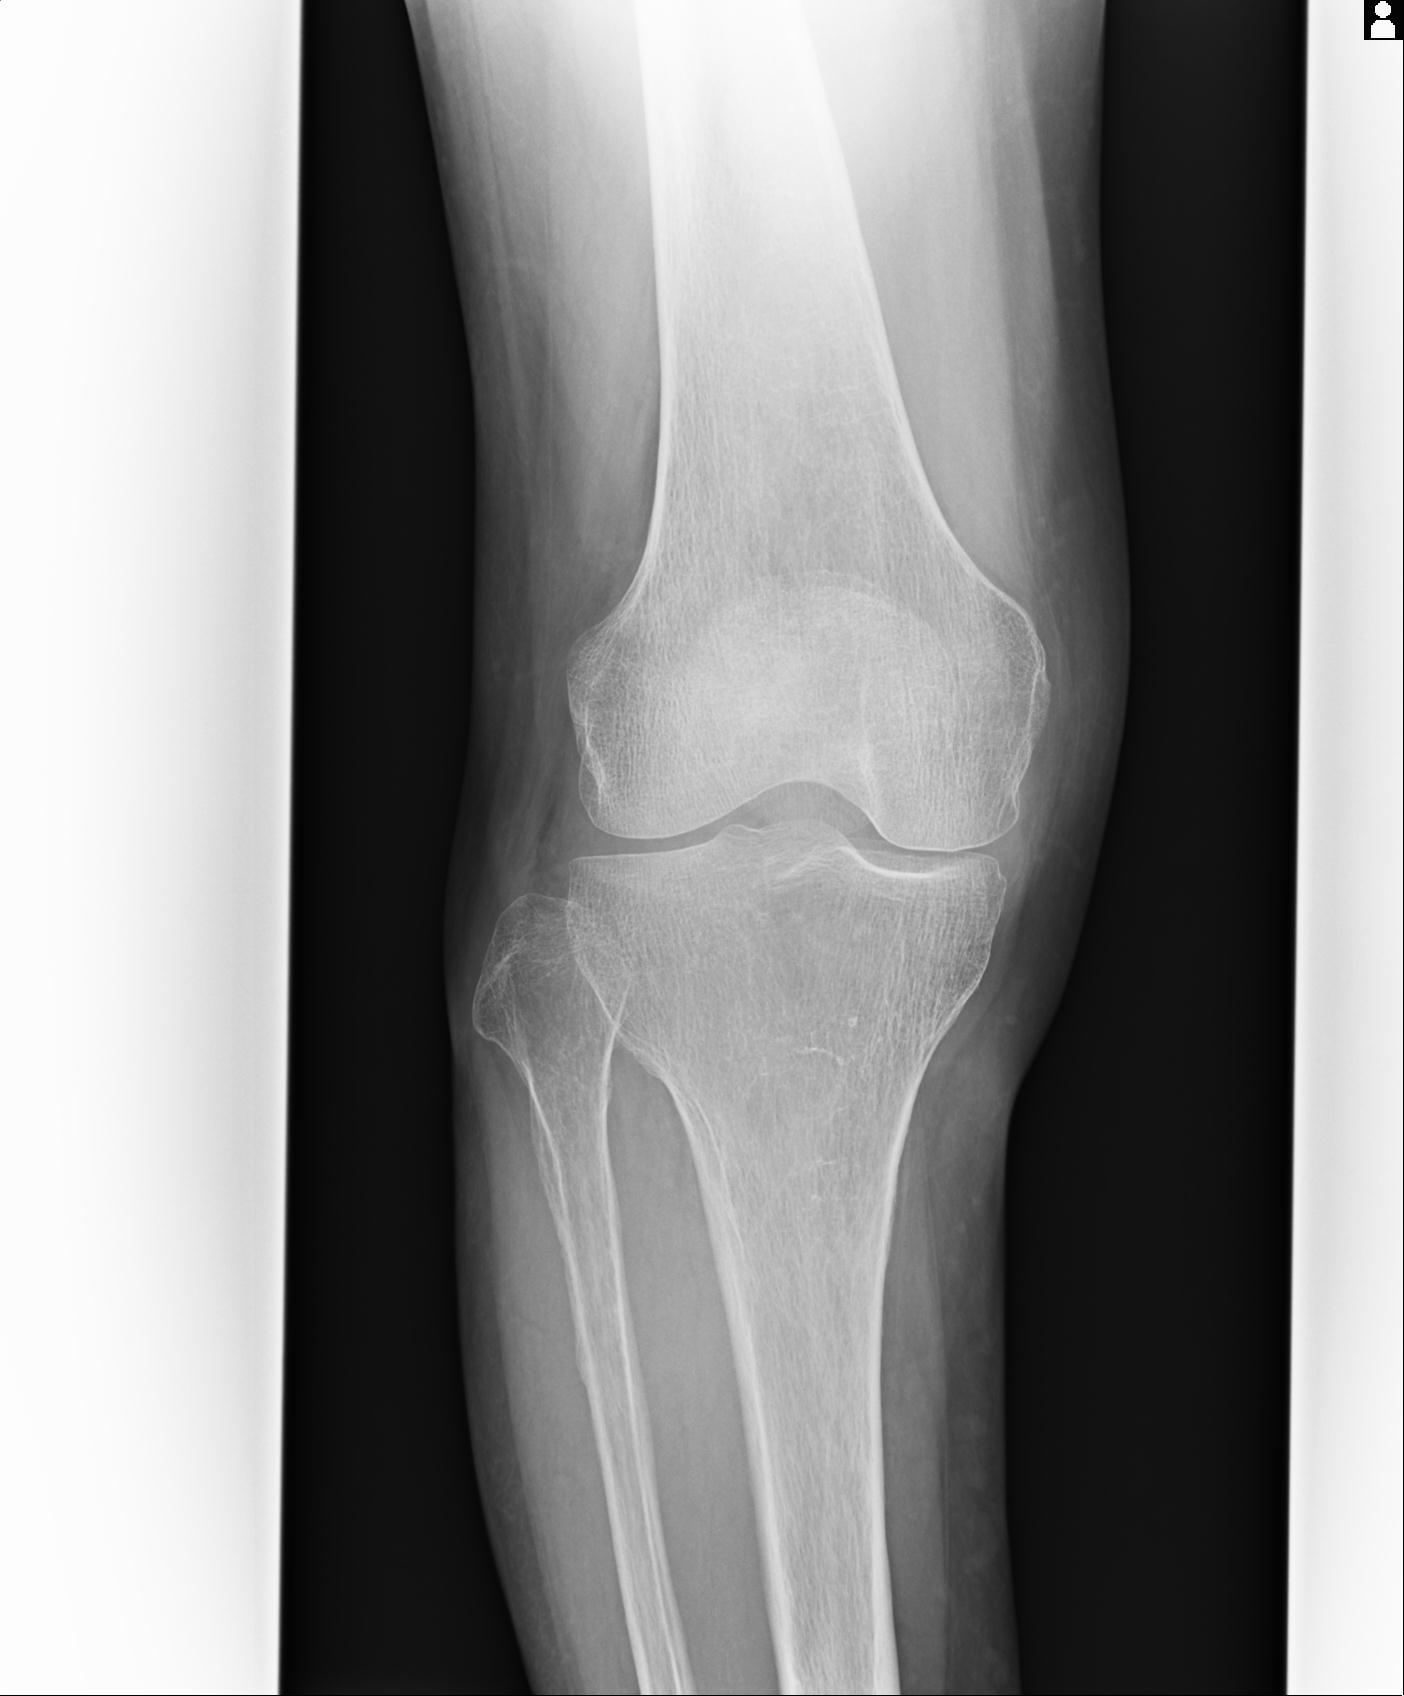

91983 11/16 左膝 2R 11/18 2R 55歳男性 脛骨骨切り術